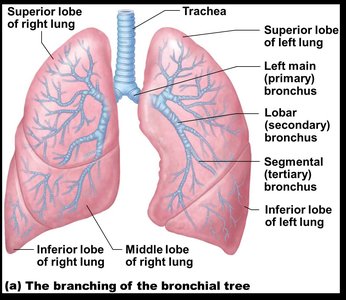

The Trachea and Bronchial Tree

The trachea is a flexible tube supported by C-shaped cartilage rings, leading to the primary bronchi, which branch into secondary (lobar) and tertiary (segmental) bronchi, and finally into bronchioles and terminal bronchioles.

Bronchi: Right lung has three secondary bronchi, left lung has two; further branching forms the bronchial tree.

The lungs are divided into lobes and segments, each supplied by its own bronchus and blood vessels. The right lung has three lobes; the left lung has two and a cardiac notch.